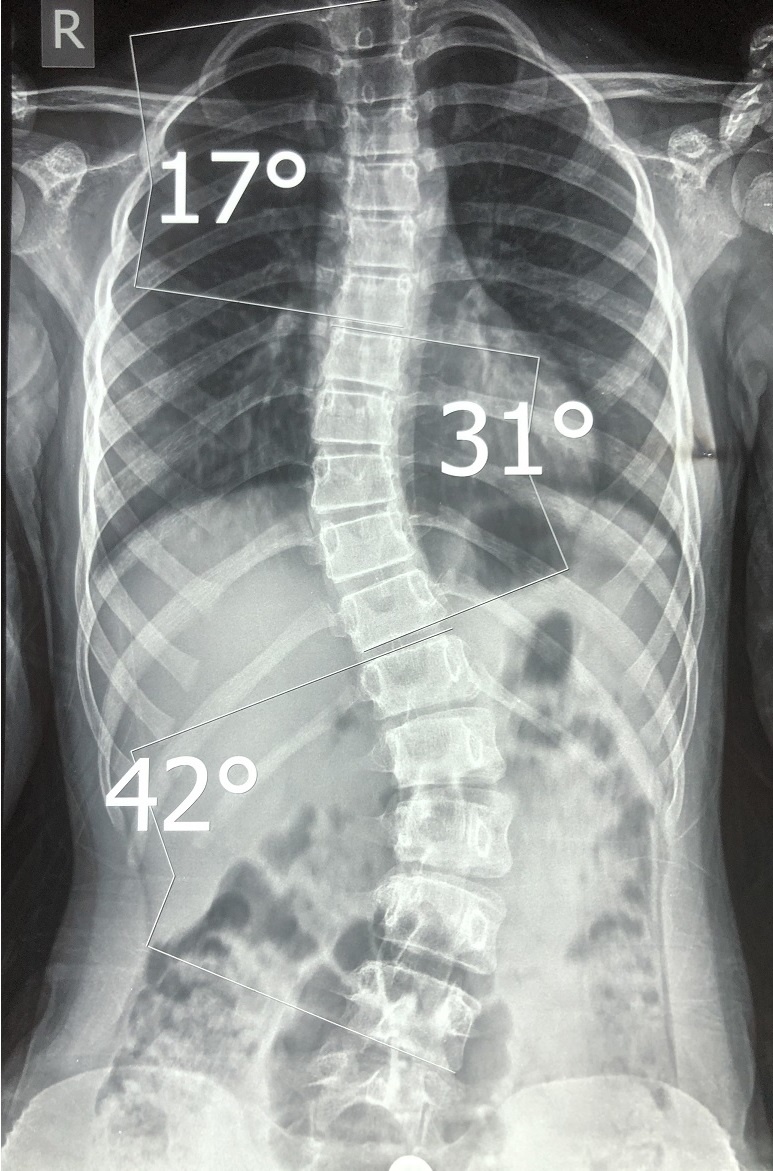

Переписка с пациентом о возможности исправить сколиоз в 23 года!

- Мне 23 года, у меня сколиоз 2 степени. Искривление очень заметно на талии, как будто перекос таза. Доктор:

- Мне 23 года, у меня сколиоз 2 степени. Искривление очень заметно на талии, как будто перекос таза.